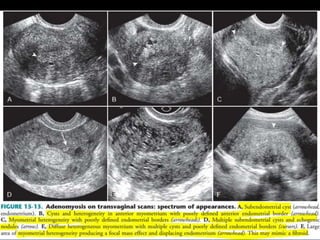

This document contains an image gallery from Dr. Mohit Goel showing various uterine anomalies and ovarian cysts. It includes images of an arcuate and unicornuate uterus, endometritis, a twisted ovarian pedicle, dermoid cysts of varying sizes and echogenicity containing hair, fat, and calcifications, and a combination dermoid cyst showing both mesh and plug structures. The gallery provides ultrasound images of different gynecological conditions for medical education and reference.